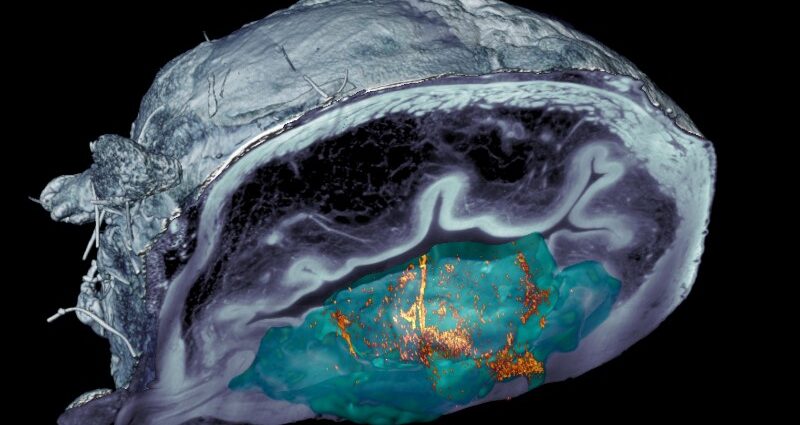

Questo nuovo studio va oltre dimostrando non solo la mobilità delle nanoparticelle nella vescica, ma anche il loro accumulo specifico nel tumore.

Questo risultato è stato reso possibile da varie tecniche, tra cui l’imaging medico con tomografia a emissione di positroni (PET) dei topi, nonché immagini al microscopio dei tessuti rimossi dopo il completamento dello studio.

Questi ultimi sono stati catturati utilizzando un sistema di microscopia a fluorescenza sviluppato appositamente per questo progetto presso l’IRB di Barcellona.

Il sistema scansiona i diversi strati della vescica e fornisce una ricostruzione 3D, consentendo così l’osservazione dell’intero organo.

“L’innovativo sistema ottico che abbiamo sviluppato ci ha permesso di eliminare la luce riflessa dal tumore stesso, permettendoci di identificare e localizzare le nanoparticelle in tutto l’organo senza una preventiva marcatura, con una risoluzione senza precedenti. Abbiamo osservato che i nanorobot non solo raggiungevano il tumore, ma vi entravano anche, potenziando così l’azione del radiofarmaco”, spiega Julien Colombelli, responsabile della piattaforma di microscopia digitale avanzata presso l’IRB di Barcellona.

Il lavoro con i nanorobot ha rappresentato una sfida scientifica significativa nelle tecniche di bioimaging per la visualizzazione di questi elementi nei tessuti e nel tumore stesso.

Le comuni tecniche cliniche non invasive, come la PET, non hanno la risoluzione necessaria per localizzare queste particelle molto piccole a livello microscopico.

Pertanto, la piattaforma di microscopia scientifica dell’IRB di Barcellona ha utilizzato una tecnica di microscopia che utilizza un foglio di luce laser per illuminare i campioni, consentendo l’acquisizione di immagini 3D attraverso la diffusione della luce in seguito all’interazione con tessuti e particelle.

Dopo aver osservato che il tumore stesso disperdeva parte della luce, generando interferenze, gli scienziati hanno sviluppato una nuova tecnica basata sulla luce polarizzata che annulla tutta la dispersione dal tessuto e dalle cellule tumorali.

Questa innovazione consente la visualizzazione e la localizzazione dei nanorobot senza la necessità di una preventiva marcatura con tecniche molecolari.

Immagine: Advances Digital Microscopy, IRB Barcellona.